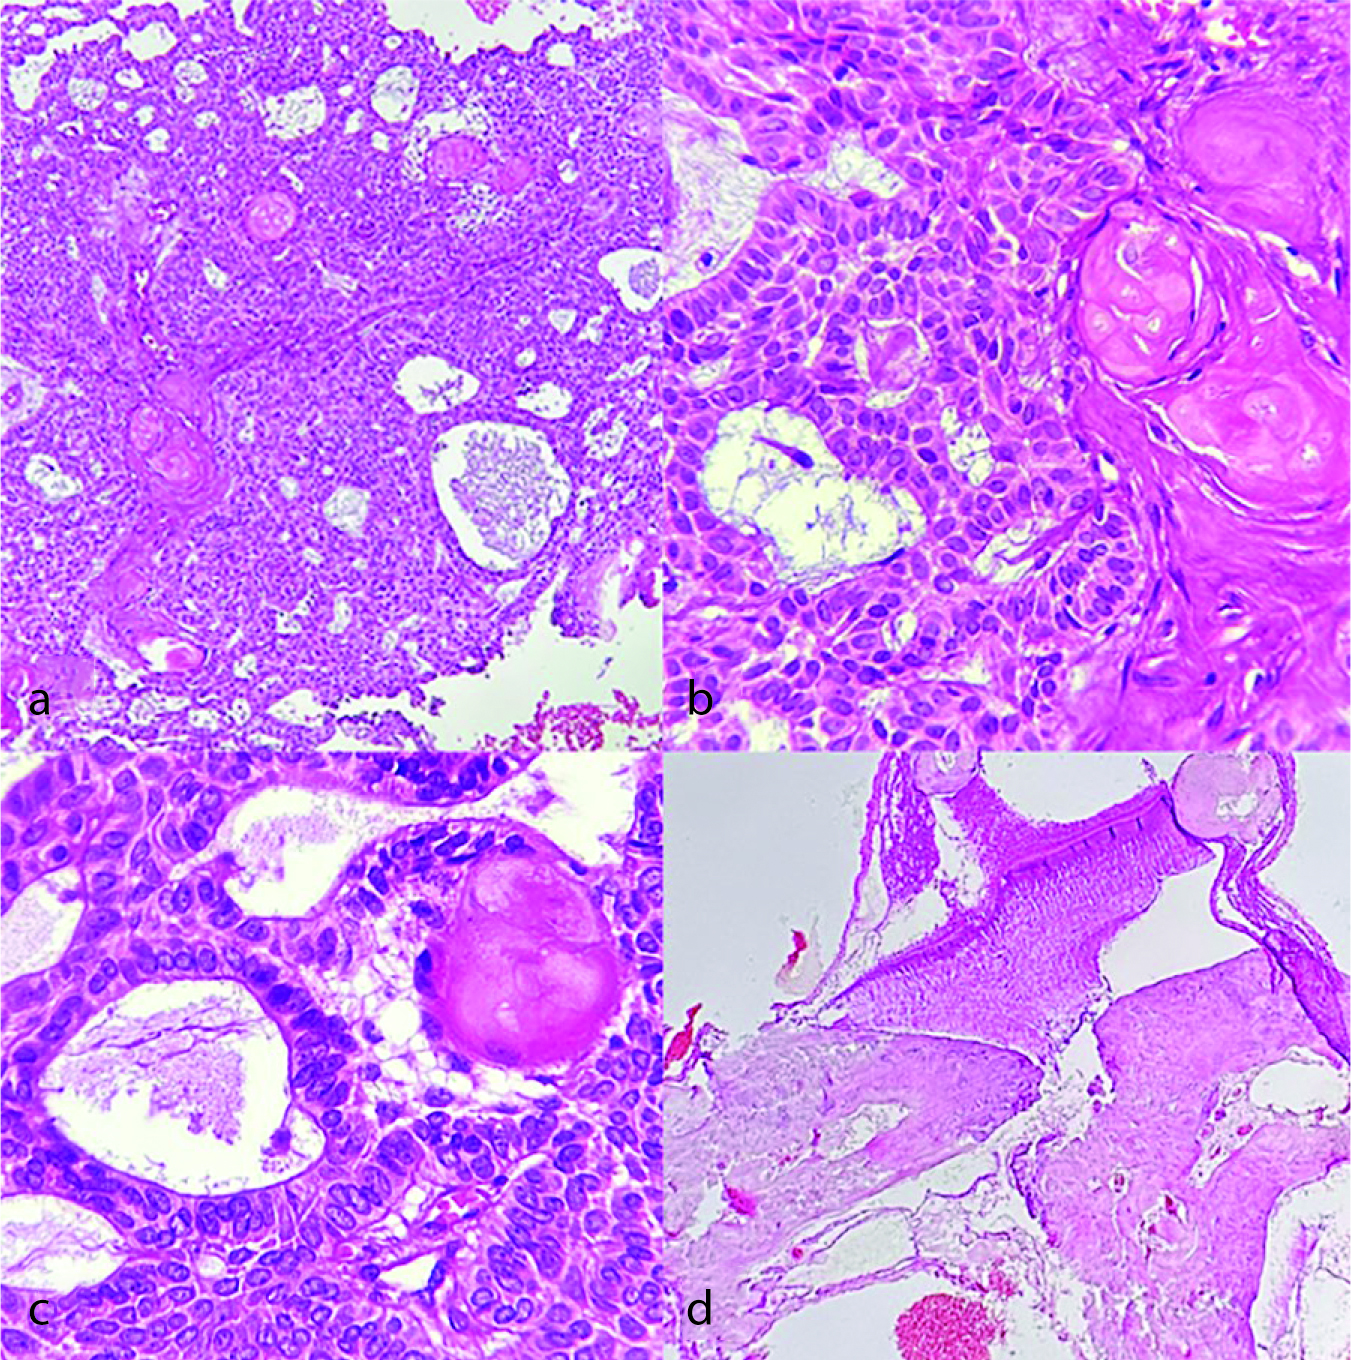

D: Complex histology which is composed of epithelial follicles packed with parakeratin/orthokeratin and keratin masses extruded into connective tissue stroma in the form of Pacinian-like stacks with or without foreign body response. Therefore, the microscopic appearance of the present case (Figure 2) is similar to the case described by Neuman et al. [ 7 ], which showed a superficial OKC with palisading basal cell layer, corrugated surface, and islands of ameloblastoma in the underlying connective tissue showing reverse polarity and apical vacuolization.

Figure 2. Histopathologic sections of odontogenic keratocyst/ameloblastoma, a: A cystic lesion lined by a parakeratinized stratified squamous epithelium with corrugated surface and palisaded basal cell layer (Hematoxylin and eosin staining, 100×), b: The cystic epithelium (arrow) and underlying ameloblastic nests with squamous metaplasia (arrow head) (Hematoxylin and eosin staining, 400×), c-d: The underlying connective tissue displays back to back ameloblastic islands with reverse polarity of peripheral cells (Hematoxylin and eosin staining, 400×, 100×; respectively)